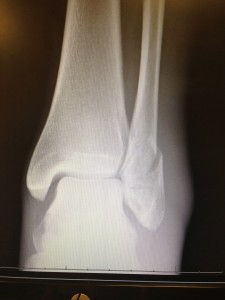

Driving to my doctor’s appointment, I optimistically wished to have a boot. That way, I could still hobble around, but my foot would be more protected. The nurse practitioner ordered an X-ray. When he saw the X-ray, he prefaced his conclusion with “go big or go home.” He then explained that my left fibula had a spiral fracture. Since the fibula bears only 15% of the body’s weight, a person can walk on it even if it’s broken. Still in good spirits, I took a picture of the X-ray to show to loved ones and friends.

A few hours later, I received my boot. As the boot tech fitted me, I showed him the picture of the X-ray. He speculated that I might need surgery, but I was sure I didn’t. After all, I was in good health other than the broken ankle. Besides, I had full social calendar and travel plans, which didn’t include a trip to the OR. A few days later, I had a pair of crutches to go along with my boot and an appointment for surgery.

Five weeks after surgery where I had six screws and a metal plate put into my fibula to help it mend straight, my doctor pronounced that my recovery had progressed so well that she was clearing me a week early to start physical therapy. I waived that in lieu of returning to yoga. After all, the whole reason I’d recovered so quickly was due to visualizing myself doing the things I’d done before the accident. The promise of returning to my former routine motivated me to heal.